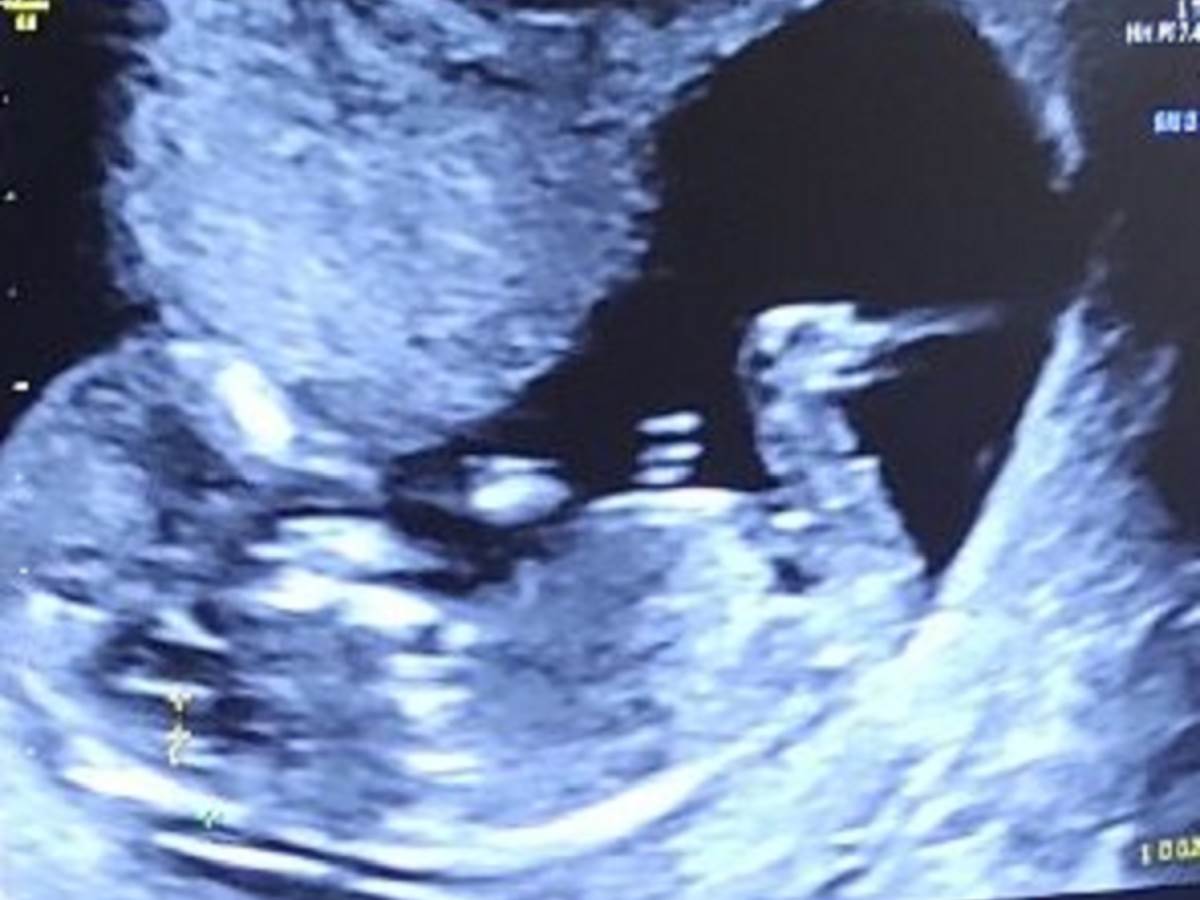

"Pozdrav za sve antivaksere i neuke kolege. Ova moja snajka je slušala skafandera, a ne vas, i devet nedelja nakon revakcine Fajzerom je dočekala da joj kažemo 'bićeš MAMA'! A pre toga četiri neuspešne VTO. Evo nova kontrola i trudnoća napreduje", poručila je.